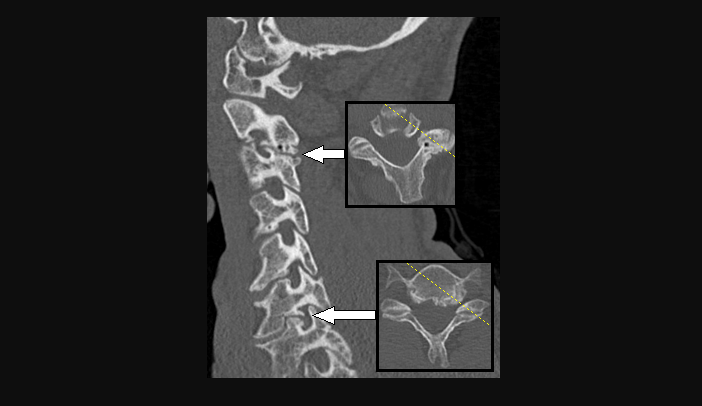

2. Spinal stenosis

When the spinal column narrows, putting pressure on the spinal cord and nerves.